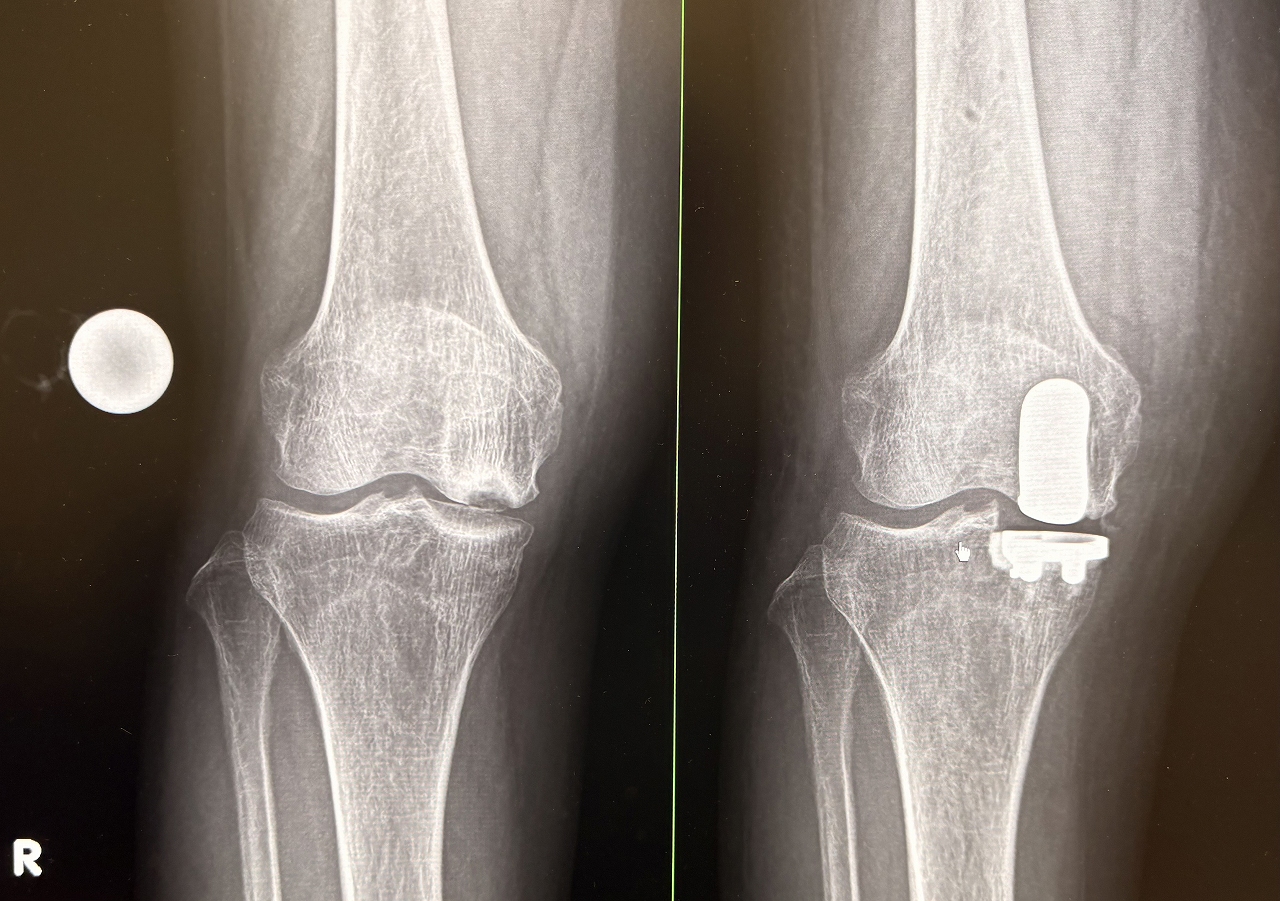

手術前と手術後のレントゲン

人工膝関節置換術は、変形性膝関節症や関節リウマチなどによって傷んだ膝関節の表面を、人工の関節部品(インプラント)に置き換える手術です。痛みの軽減や歩行能力の改善を目的として行われます。

手術では、大腿骨や脛骨(必要に応じて膝蓋骨)の骨の表面を整え、金属やポリエチレンなどでできた人工関節を設置し、骨セメントなどを用いて固定します。これにより、関節の動きをなめらかにし、日常生活動作の改善を目指します。

また、当院で近年、症例数が増加しているUKA(単顆置換術)は、TKA(全置換術)と比較して、置換が必要な部分のみに手術範囲を限定できるという特徴があります。そのため、相対的に骨の温存性が高く、前十字靱帯をはじめとする靭帯や健常な関節面を残すことが可能です。これにより手術侵襲が抑えられ、術後の違和感が少なく、早期の機能回復が得られやすいとされています。

実際に、無作為比較試験や国内外の臨床報告において、UKA(単顆置換術)はTKA(全置換術)と比較して、術後6週間から3か月にかけて、歩行能力などの日常生活動作に関連する回復が早く、術後疼痛の軽減や入院期間の短縮が期待できる手術法であることが示されています。

一方で、UKAは一般的にTKAと比べて手術視野が限られ、健常な骨や靭帯を温存しながら関節のバランスを精密に調整する必要があるため、より高い手術精度が求められる術式でもあります。

UKA(単顆置換術)

左:UKA(単顆置換)右:TKA(全置換術)